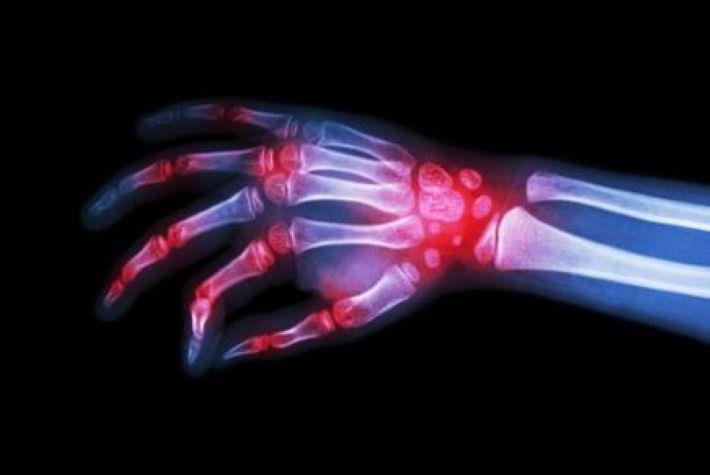

צילום רנטגן של מפרקים מודלקים, לפלונומיד (ערבה) לטיפול בדלקת פרקים

צילום: shutterstock